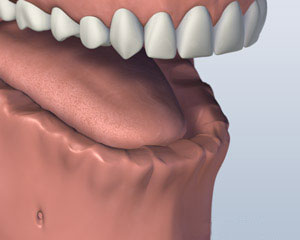

虽然很多患者都没有戴上假牙的问题, 有些人觉得很难穿,用较低的假牙吃. 一些 种植体支持的替代选项 可如果你缺少你所有的下牙.

您是否丢失了所有你的下牙?